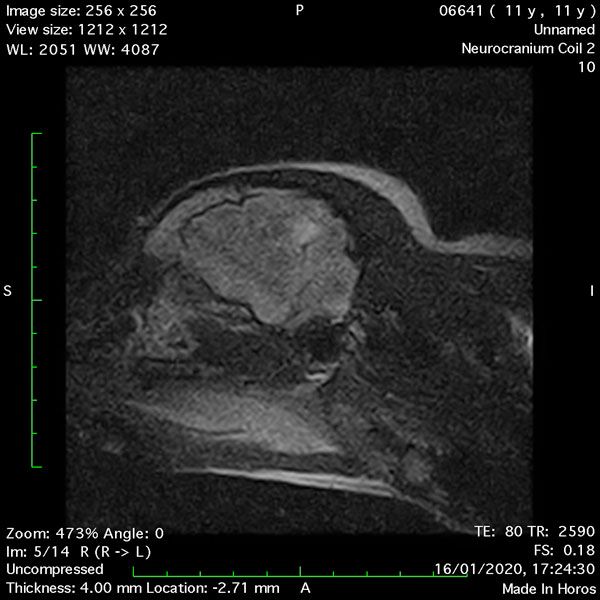

- Sagittal T2 – Turbo Spin Echo-S (Figure 7);

MRI images were viewed in DICOM format (Digital Imaging and Communications in Medicine) (Figures 1-7) and assessed in-house under the guidance of a board-certified radiologist. The series were evaluated for changes in intensity in the T1- and T2-weighted sequences (T1w and T2w, respectively). There was a 4mm x 7mm x 7mm intra-axial, wedge-shaped hyperintense reasonably-well demarcated region in the right cerebrum visible in the T2w images (Figures 2-3). This was consistent with a focal infarct. No contrast enhancement, anatomical abnormality nor space occupying lesion was noted in the T1w sequences (Figure 1, Figure 4). There was no observed pathology on assessment of the FLAIR images (Figure 5).

Figures 1-7: Images obtained with MRI depicted in sequential order and assessed under the guidance of a board-certified radiologist in-house.